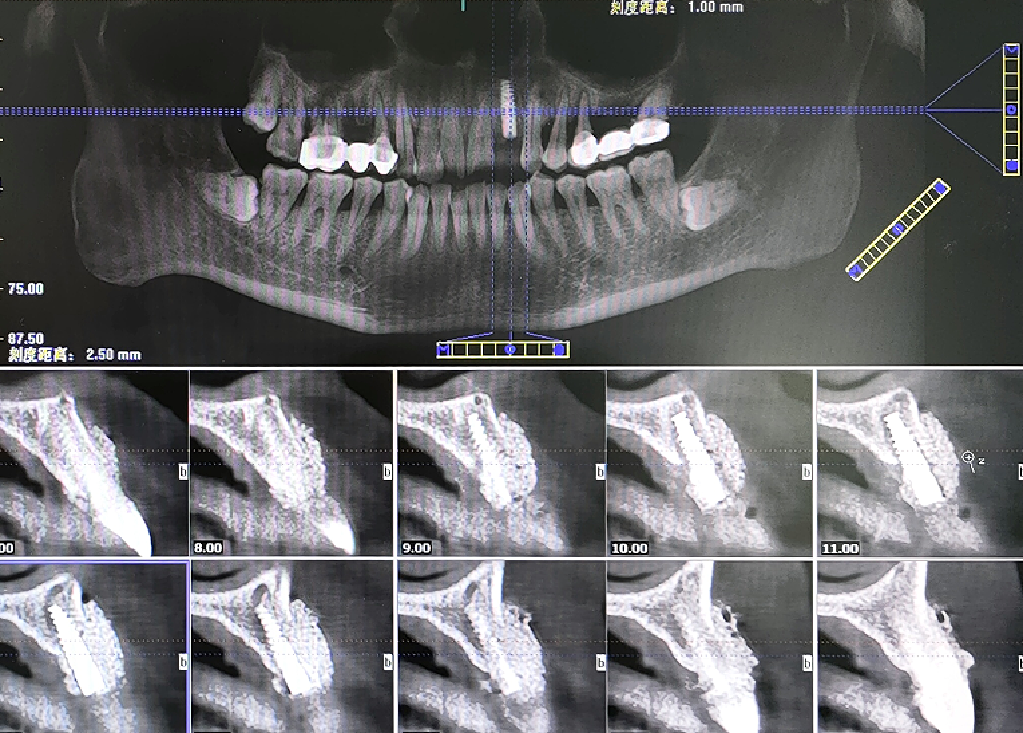

术前CBCT

21颊侧牙槽骨吸收至根尖,腭侧牙槽骨吸收至根尖1/3,根周可见低密度影。牙槽嵴宽度6.41mm。

局部反合、患牙长期牙周病变,骨质缺损,但软组织无明显缺失,为II类拔牙窝形态。

22冠状位CBCT情况

唇舌牙槽嵴宽度6.41mm,垂直骨缺失1/2,软组织无垂直向缺失。

术后即刻CBCT

术后CBCT

术前术后CBCT对比

唇侧过量植骨希望最终能够实现存量骨组织>2mm。

术后4.5个月CBCT

术后即刻与术后4.5个月CBCT对比

可见种植体唇侧顶端有一定骨粉吸收,但仍在预期范围内。